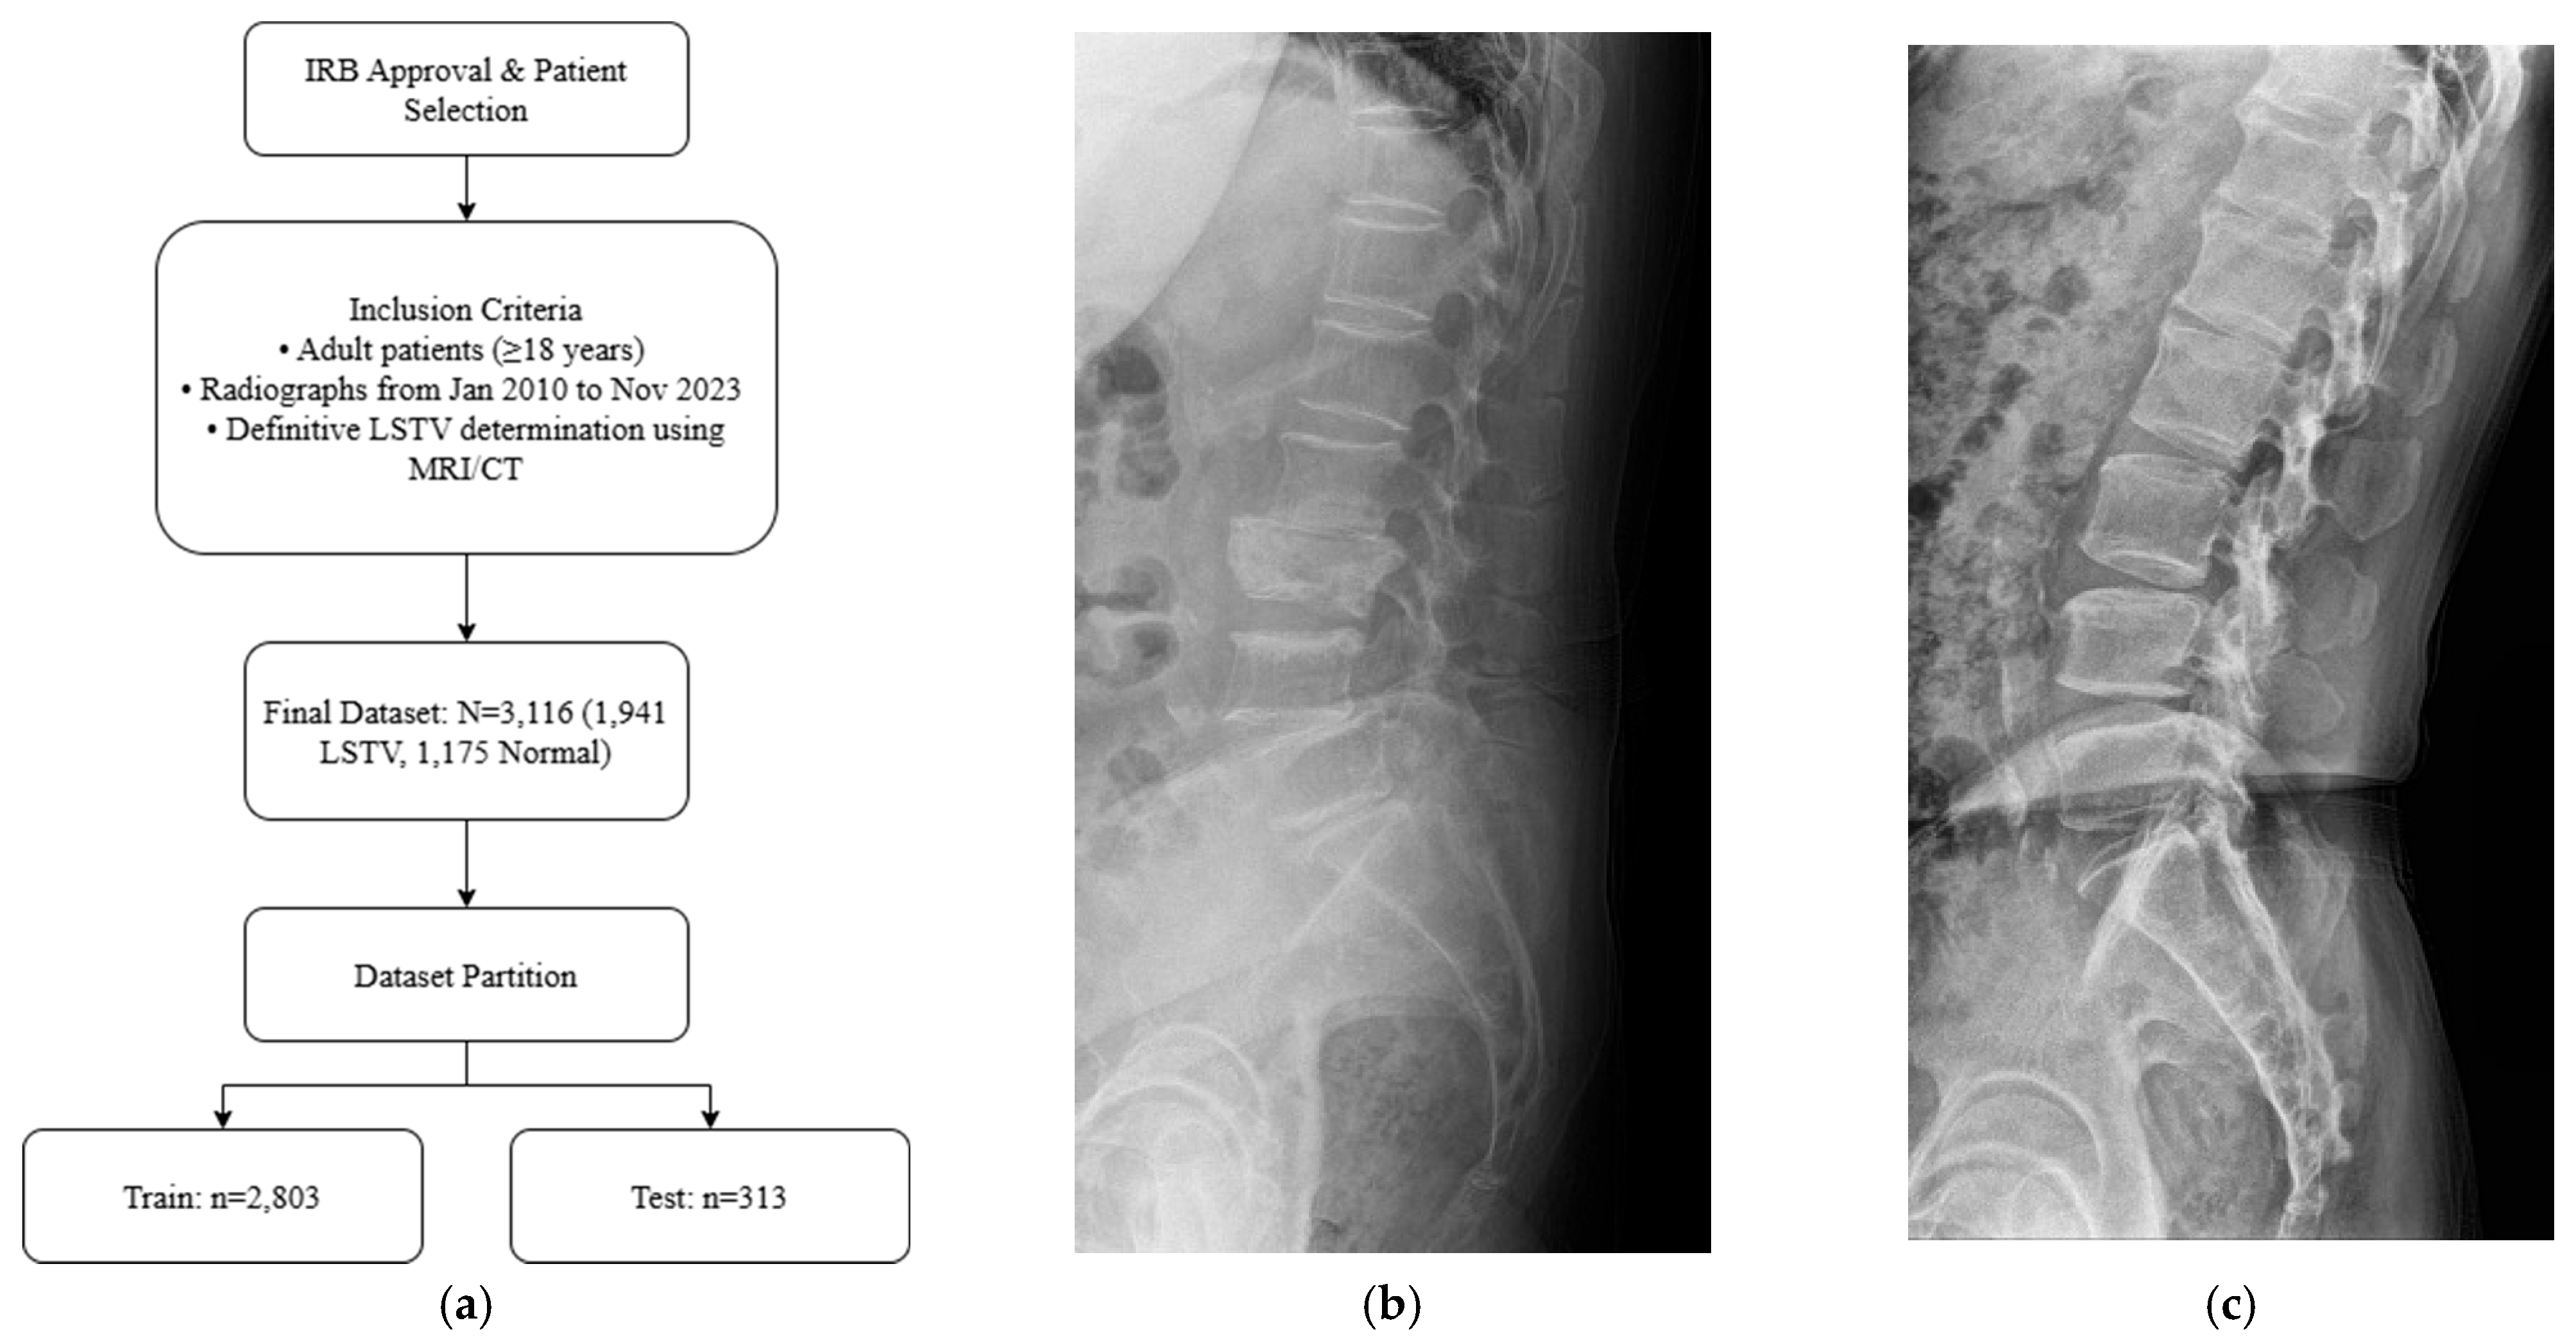

Adult patients (≥18 years) who underwent standing lumbar lateral radiography at a single tertiary hospital between January 2010 and November 2023 were included for this retrospective study. All standing lumbar lateral radiographs were acquired using digital radiography systems from multiple manufacturers, including Philips Healthcare (Amsterdam, The Netherlands), Canon Medical Systems Corporation (Ōtawara, Tochigi, Japan), Samsung Electronics Co., Ltd. (Suwon, Republic of Korea), and Fujifilm Corporation (Tokyo, Japan). To establish a definitive ground truth, only patients for whom the presence or absence of LSTV could be unequivocally determined using whole-spine MRI, CT, or radiographs that allowed for accurate vertebral enumeration were selected. The presence or absence of LSTV was labeled based on the MRI conclusion that explicitly mentioned transitional vertebra, lumbarized, sacralized, lumbarization, or sacralization. Patients were excluded if they had a history of lumbar surgery with instrumentation, severe spinal deformities or pathologies obscuring local anatomy, or poor image quality (Figure 1a). The final dataset was stratified, with 10% reserved as an independent test set and the remaining 90% subjected to stratified 5-fold cross-validation for model development and validation. Representative examples of each class are shown in Figure 1b,c, illustrating the visual differences between LSTV cases and normal lumbosacral anatomy. These examples highlight the morphological variability that makes manual identification challenging.

After applying the inclusion and exclusion criteria, the final dataset comprised 3116 standing lumbar lateral radiographs. Of these, 1941 (62.3%) were diagnosed with LSTV and 1175 (37.7%) were classified as normal. The dataset was divided into a training set (n = 2803) and an independent test set (n = 313). There were no significant demographic differences between the two sets.

Figure 1. (a) Flow diagram of patient selection and dataset partitioning. Adult patients (≥18 years) with standing lumbar radiographs and MRI/CT-confirmed LSTV were included (n = 3116; 1941 LSTV, 1175 normal) and divided into training (n = 2803) and independent test (n = 313) sets. (b) Representative lateral radiograph showing LSTV with lumbarization of the S1 vertebra and morphological alteration of the L5–S1 junction. (c) Representative radiograph of a normal lumbar spine illustrating a well-defined lumbosacral junction and distinct separation between the L5 vertebra and sacrum.